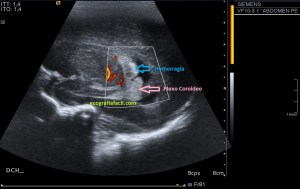

En la imagen 3 ves una imagen de un lipoma, mide 7 cms, la huella de la sonda mide 5cms, la «panoramic view» posee una regla centimetrada que sigue el contorno de la imagen, justo en la profundidad de la misma y lo marca la flecha amarilla. La profundidad la marca la flecha roja y la flecha blanca marca el rango centimetral de los 5cms, fíjate que la línea blanca es ligeramente mayor cada 5 cms. Sirve de referencia, como en la imagen 4 donde ves una colección en el glúteo de más de 10 cms.